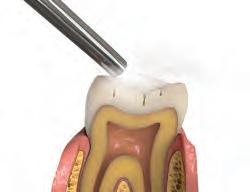

Sable Seek caries indicator contains FD&C dyes, and Seek caries indicator contains D&C dyes in a glycol base. Both are used to stain carious and demineralized dentin.

Seek and Sable Seek caries indicators stain carious and demineralized dentin and can be very useful for difficult-to-see areas, for example; undercuts of preparations, dark dentin, areas along the DE junction, etc. Green Sable Seek caries indicator helps visualization of decay in deep caries cases to help avoid pulp exposures.

PROCEDURE

dentin) with slow-speed round bur or excavator. To control overexcavating near the pulp, remove final portion of caries with hand excavator.